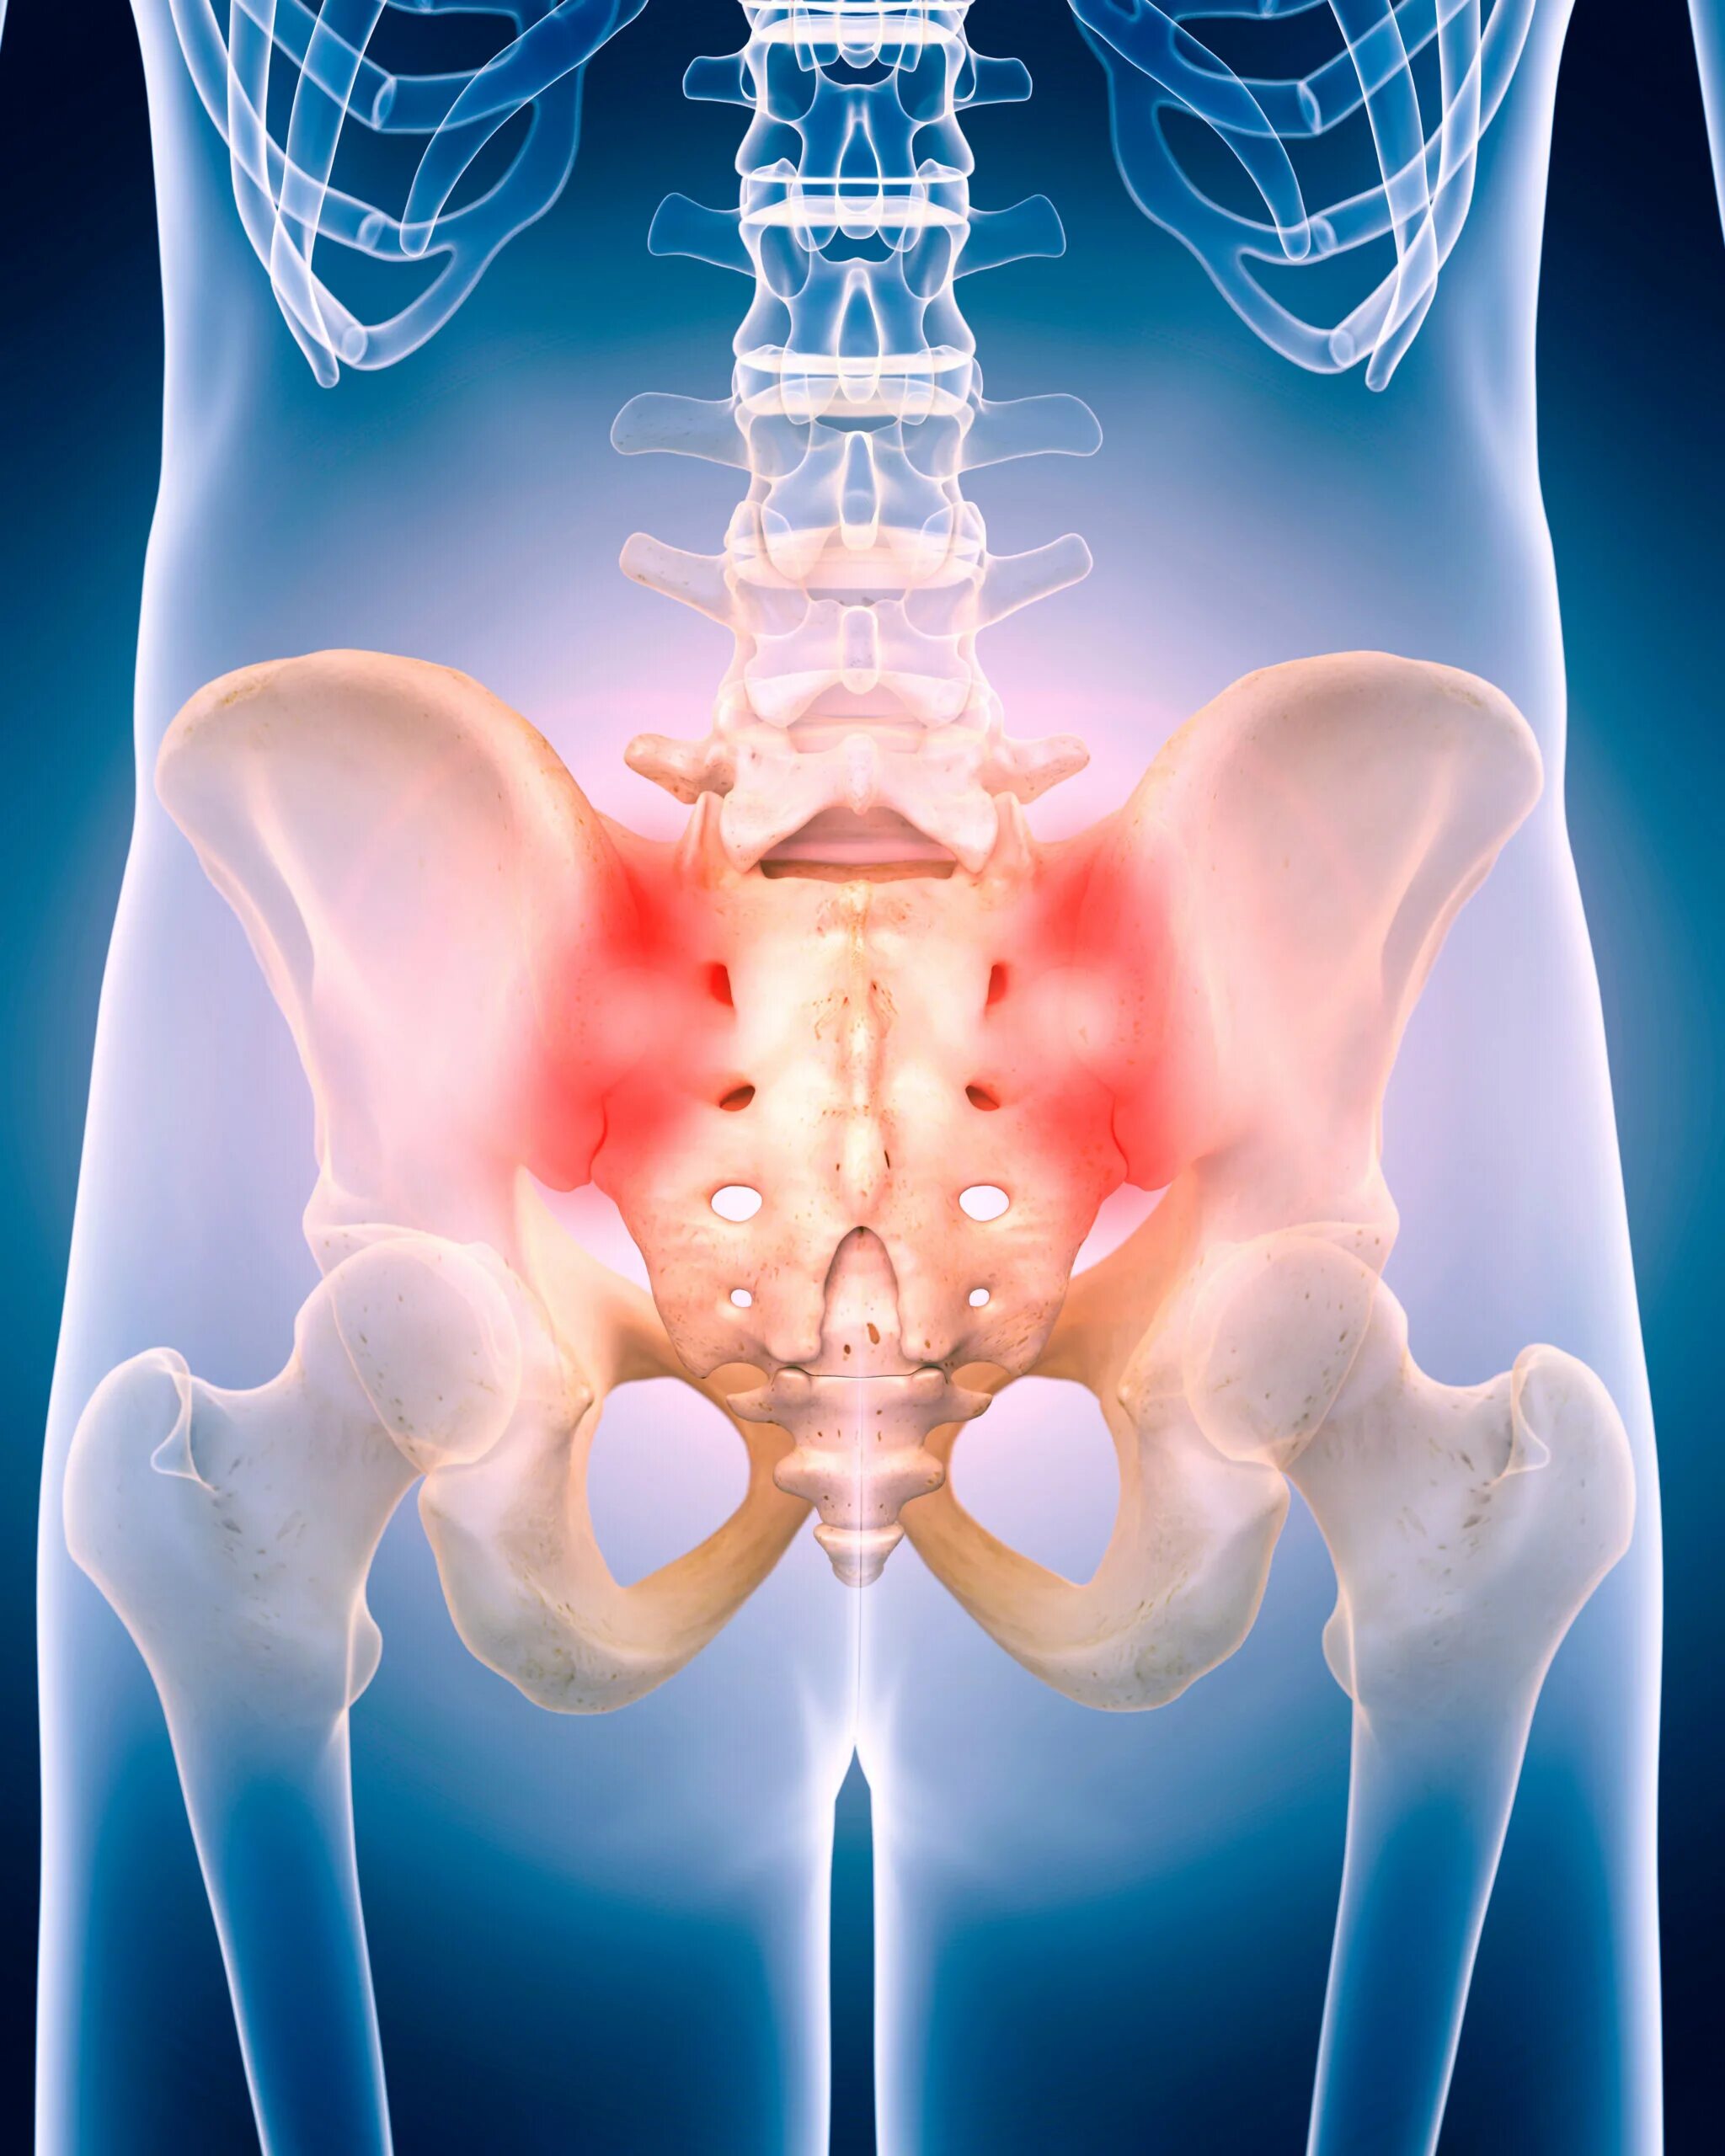

Воспаление подвздошных сочленений